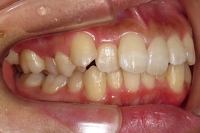

CASE3

前歯1本だけが出ています、矯正で治りますか?

(23歳/女性)↓

概要・担当医コメント:

前歯の唇側傾斜/マルチブラケット装置/非抜歯

動的治療期間15ヶ月(15回)/費用概算:60万円.

歯列アーチの形態修正に必要なスペースを微量のエナメル質の研磨により創生し,当初の計画通りに歯を移動させました.